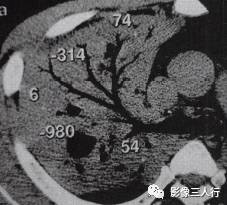

胸部CT图像显示,在含气少的致密肺的背景上见到含气的支气管,表现为两种形态: ①在大片肺实变病灶内的细条状空气密度影;②直径Imm的小泡状空气密度影,连续的几 个层面都能出现(图2、图3)。该征象表明:①近侧气道通畅;②肺泡内的空气经吸收(肺不张)或取代(肺炎、肺癌),或两者综合而消失。通畅含气的支气管在肺泡实变高 密度区内表现为管腔内低密度充气轮廓。